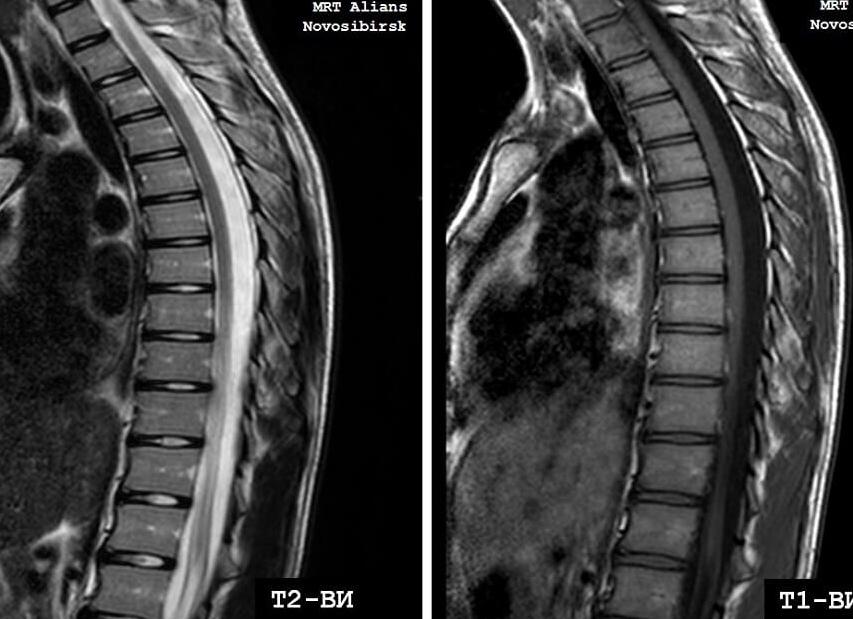

Межпозвоно́чная грыжа (межпозвонко́вая грыжа, грыжа межпозвоночного диска) — это смещение пульпозного ядра межпозвоночного диска с разрывом фиброзного кольца. Наиболее часто встречаются грыжи межпозвонковых дисков пояснично-крестцового отдела позвоночника (150 случаев на 100 000 населения в год), значительно реже наблюдаются грыжи в шейном отделе позвоночника, наиболее редки — в грудном отделе. Хотя грыжи относительно редко требуют хирургического вмешательства, тем не менее в США ежегодно проводится более 200 тысяч, а Германии 20 тысяч вмешательств. В 48 % случаев грыжи локализуются на уровне L5-S1 пояснично-крестцового отдела, в 46 % случаев — на уровне L4-L5, остальные 6 % на других уровнях или на нескольких уровнях пояснично-крестцового отдела.